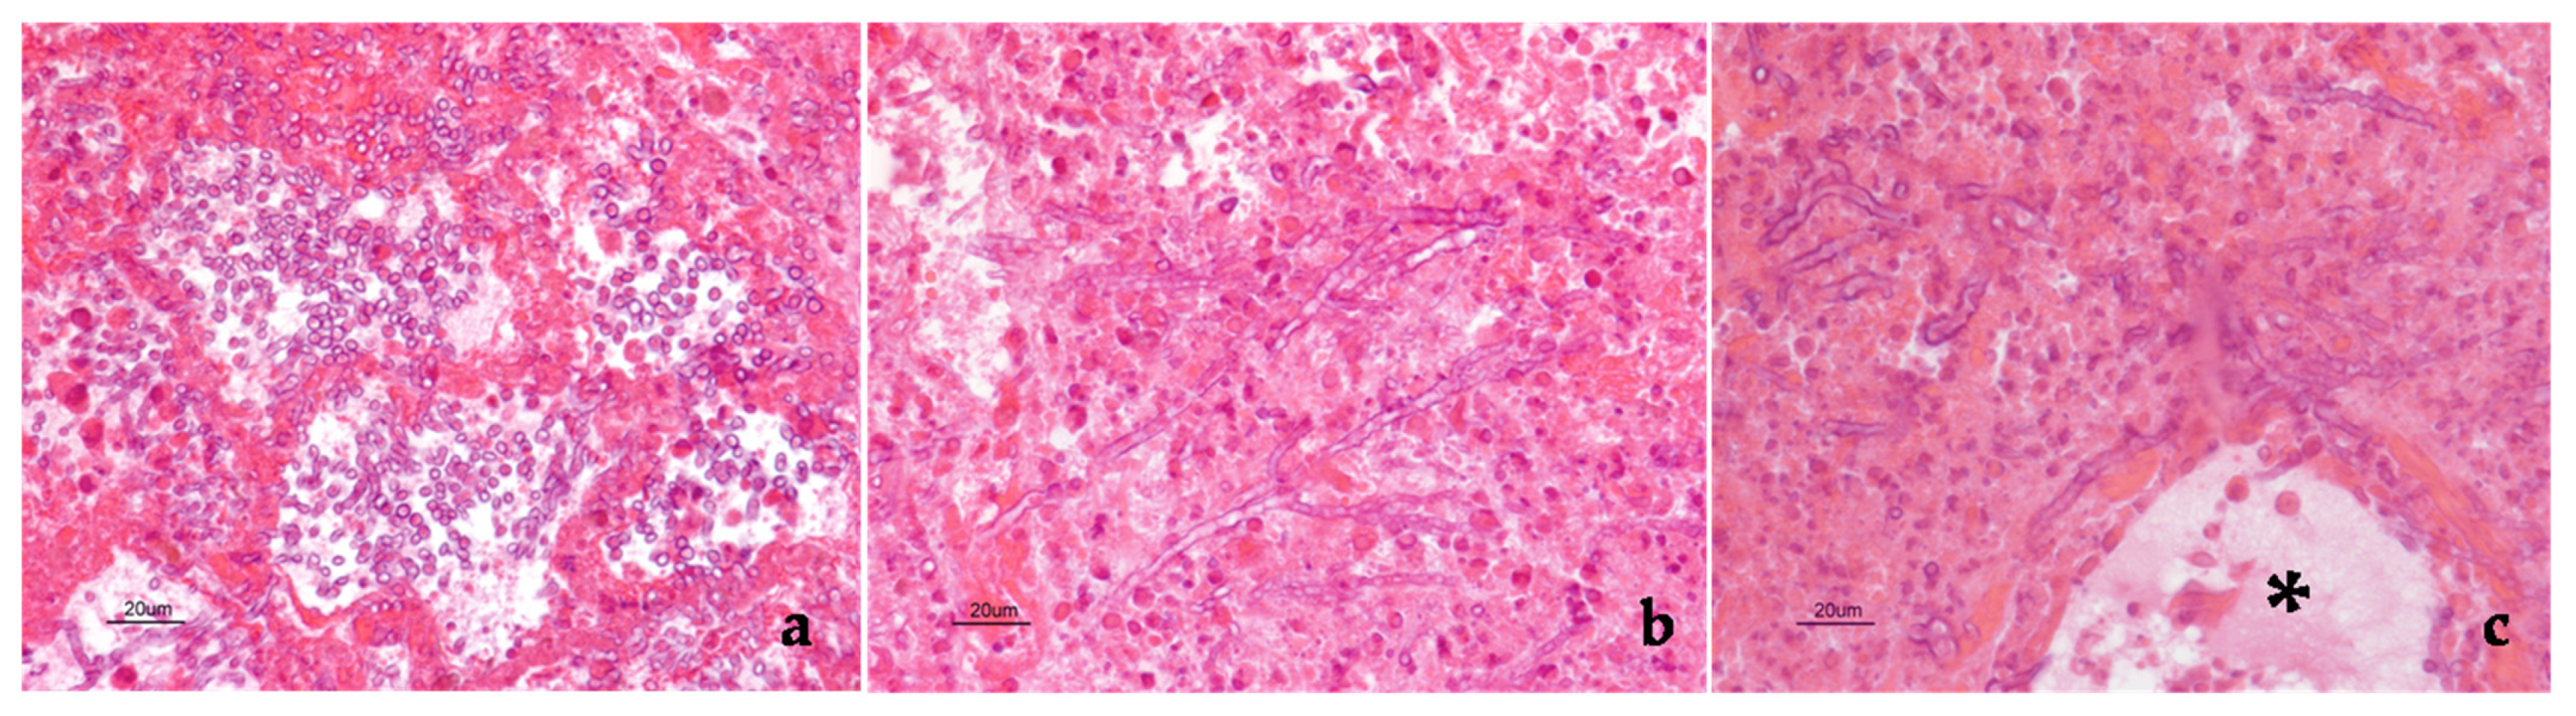

Aspergillus Section Fumigati Pneumonia and Oxalate Nephrosis in a Foal

2. Case Description